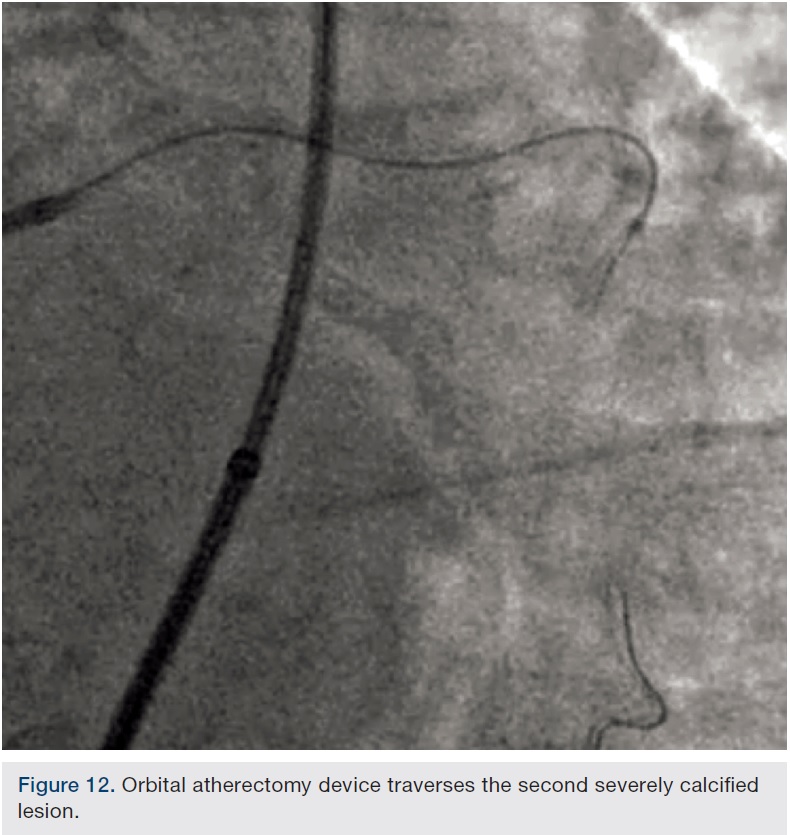

Preparation of this vessel was completed with atherectomy in order to facilitate stent delivery and optimal stent expansion. The Diamondback 360 orbital atherectomy system (CSI) was chosen, given the severe tortuosity. With the orbital device, there is a leading edge bushing ahead of the “working area” of the device, which prevents the wire from being cut on tortuous turns. A 1.25 mm device was used and was delivered around the most extreme portion of the tortuous vessel where the critical lesion was located. Several runs on low and high were performed (Figures 10-11). We then dilated the lesion with a 3.0 mm balloon, and angiography showed adequate balloon expansion (Figure 13). A GuideLiner (Vascular Solutions) was placed prior to stent delivery to increase chances of stent delivery, but also to decrease the chance of stent embolization if the stent had to be withdrawn. A 4.0 x 28 mm Promus Premiere stent (Boston Scientific) was then delivered fairly easily with good stent expansion (Figure 14) and the procedure was finished safely (Figure 15).